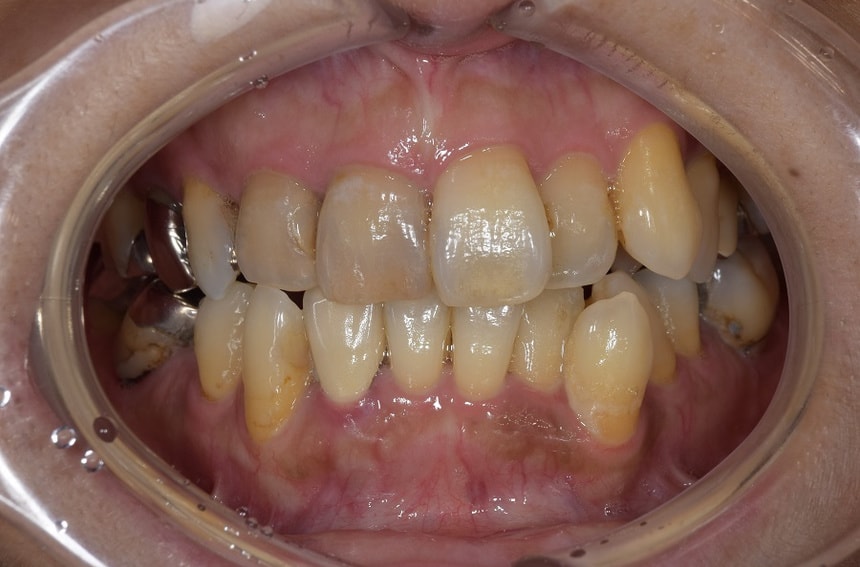

部分矯正を含めた全顎的な治療

前歯の治療前後

最小限の矯正治療や過去に治療した銀歯の隙間から虫歯になった歯や神経の再治療を行いました。もう少し修正が必要なのですが、部分矯正も含め長い治療になり、とりあえずはお疲れさまでした。

治療は、僕たちは当然ですが、患者さんにも頑張って頂いて初めてうまくいくものかなとも思います。定期的に通院していただいたり、治療が間延びしないことも治療がうまくいく要因の一つのように感じます。

治療が終了して終わりではなく、維持するためこれからメンテナンスが、始まると思っていただければ幸いです。現状が、できるだけ長期に維持できればと考えています。